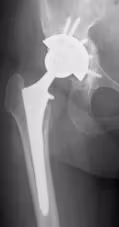

④人工股関節後感染

難治性の人工股関節置換術後感染に対し、抗生剤入りセメントモールドを使用した二期的再建術を行い、股関節機能を再建します。